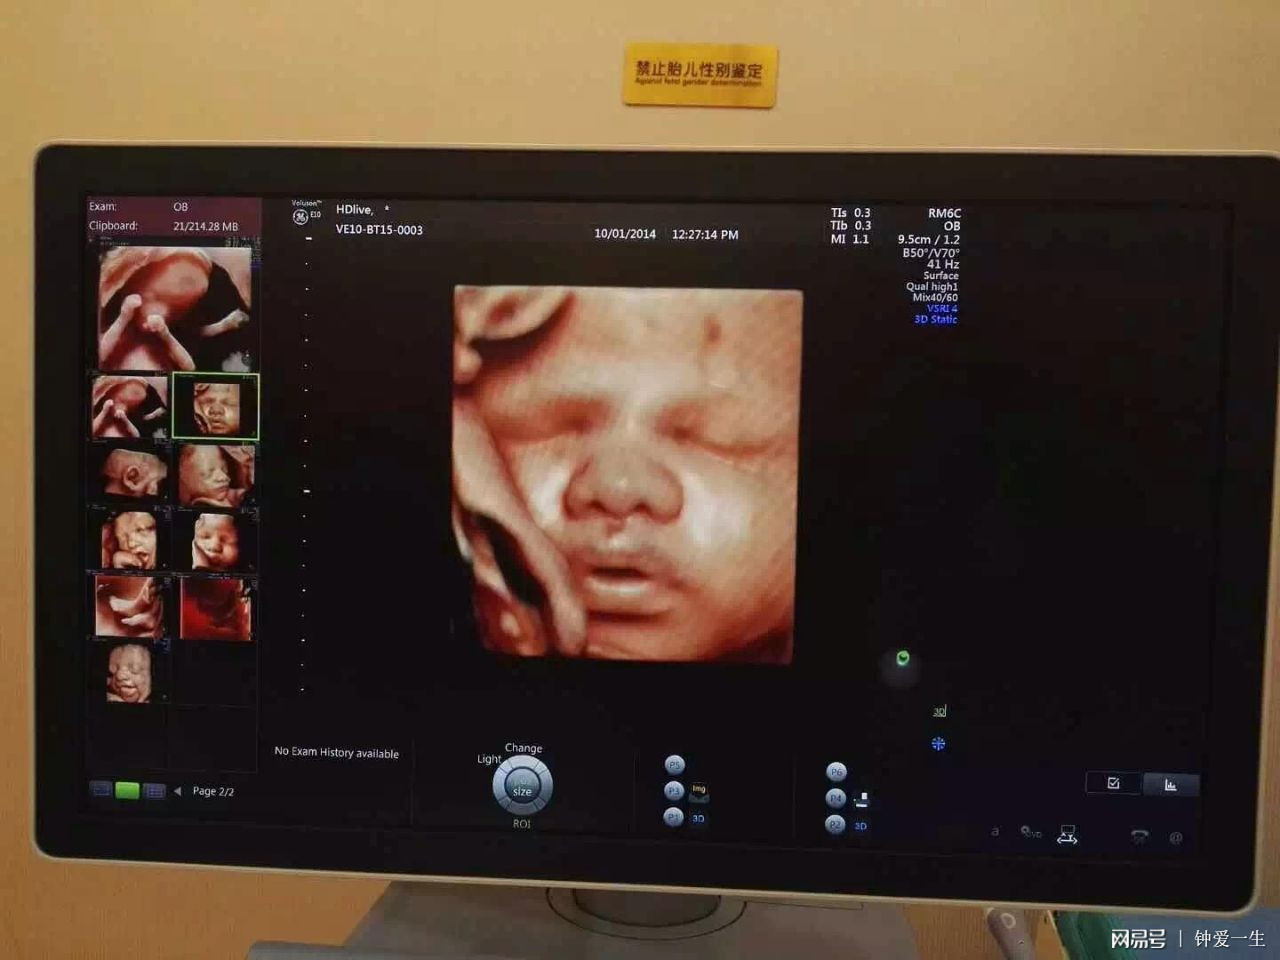

准妈妈妈小西,由于是头胎没有什么经验,在孕期极为不注意,对补充营养的意识不强,导致在做四维时才发现胎儿是变形的,一家人堕入迷雾中!